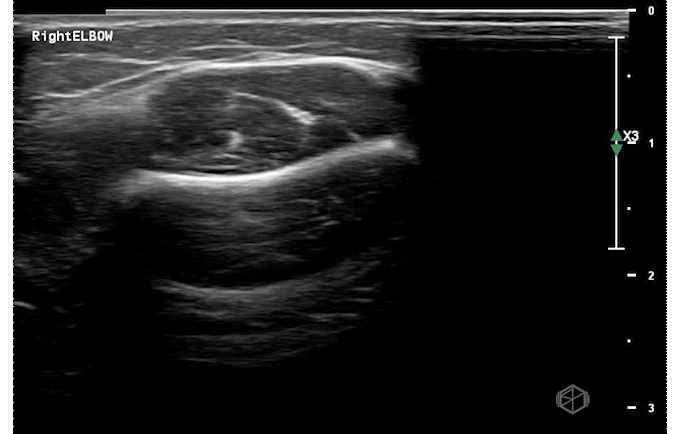

Our second SonoProp goes to Dr. Siri Tummala. Dr. Tummala scanned a 4-year-old male with LEFT elbow pain after injuring himself while going down a slide. Using the linear probe she obtained two views of the supracondylar area as seen below and compared it to the right elbow.

The LEFT elbow demonstrates an elevated fat pad with heterogeneous material within it representing lipohemarthrosis, while the right elbow demonstrates a normal posterior fat pad.

Diagnosis — Left elbow supracondylar fracture

• Ultrasound has high sensitivity (98-100%) and specificity (70-93%) for a supracondylar fractures (23142008, 26815896, 27277459). Lipohemarthrosis, a prominent dorsal fat pad are highly indicative of supracondylar fractures. Cortical disruption can be seen as well. When XR and US are both negative, the possibility of fracture can be rule out definitively (27697406).

• While it does not replace X-ray, ultrasound can be used when there is a high suspicion and the X-ray is equivocal or read as negative to diagnose occult supracondylar fractures.